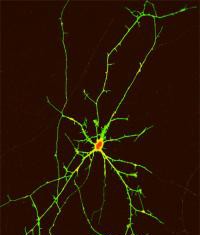

Las células madre apuntan a un posible tratamiento para la enfermedad...

La enfermedad de Huntington, el debilitante trastorno congénito neurológico que progresivamente le roba los pacientes de la coordinación muscular y la capacidad cognitiva, es...